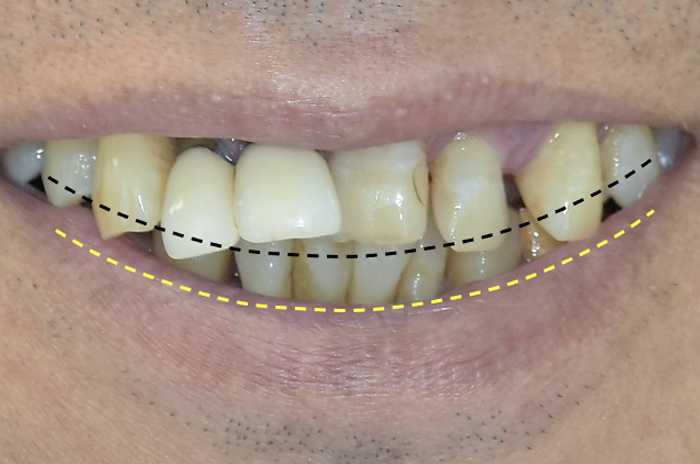

インサイザルエッジポジション

の決定

治療用義歯を作るために、まずは前歯の位置を決定します。

解剖学的ランドマーク(歯がここにあるべき、という口の中の印)、笑った時の口唇の上がり具合などを基準とします。